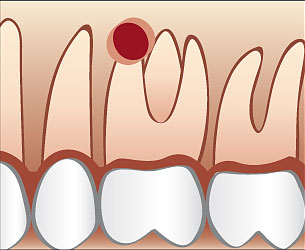

Ablauf einer Wurzelspitzenresektion

Üblicherweise wird eine Wurzelspitzenresektion in örtlicher Betäubung durchgeführt. Die Schleimhaut wird vom Knochen abgelöst und die Wurzelspitze mit Hilfe eines Spezialbohrers freigelegt. Anschließend wird die Wurzelspitze abgetragen und der Entzündungsherd oder eine eventuell vorhandene Zyste entfernt. Eine antimikobielle photodynamische Therapie mittels Softlaser kann für eine zusätzliche Keimreduktion sorgen. Bei Bedarf werden die dünnen Kanäle im Bereich der Wurzelspitze mit speziellen Ultraschallgeräten erweitert mit einem speziellen Füllungszement abgedichtet. Danach wird dessen Dichtheit überprüft und die Schleimhaut vernäht.